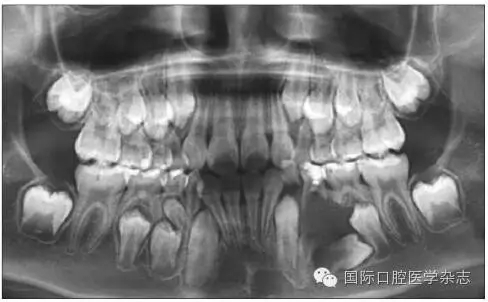

1.1.3   對(duì)牙弓長度的影響   乳牙齲病引起牙弓長度的變化并不只在乳牙因齲早失后,而是在乳牙發(fā)生鄰面齲之時(shí)即可發(fā)生。乳磨牙及乳尖牙鄰面的齲壞可引起牙冠近遠(yuǎn)中徑縮窄,造成鄰牙向缺隙處移動(dòng)、牙弓長度開始減?。▓D1),這樣會(huì)引起日后恒牙列的擁擠與牙列不齊。在兒童口腔健康管理的理念指導(dǎo)下,應(yīng)盡早治療乳牙齲病,特別是乳磨牙鄰面齲,盡量恢復(fù)患牙的外形和咀嚼功能,維持牙弓長度。對(duì)因齲壞牙而導(dǎo)致牙弓縮短的病例,可行間隙擴(kuò)大矯治器(space regain appliance)以恢復(fù)牙弓長度,避免日后牙列擁擠的出現(xiàn)或減輕擁擠程度[2]。

圖1   下頜第一、第二乳磨牙重度齲壞,牙弓長度減少

Fig 1   Severecaries of the first and second mandibular primary molar  intraoral arch length lessened